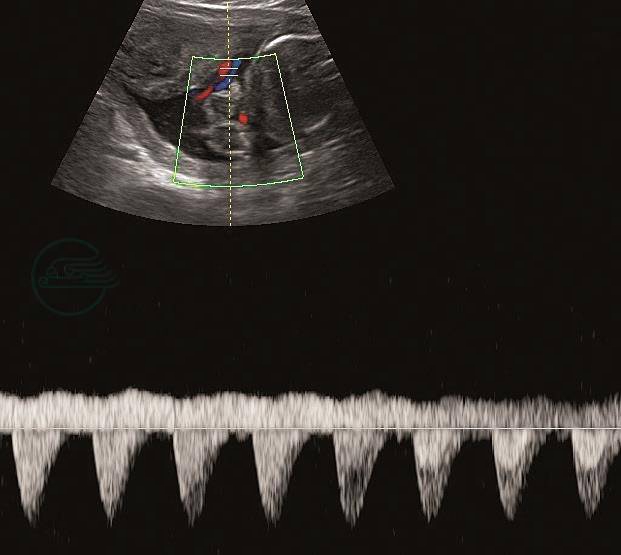

(1)脐动脉:是了解胎盘功能的重要指标。当胎盘功能不良时,会出现舒张期血流降低、搏动指数(PI)增高,舒张末期血流消失甚至反向。当EFW小于第10百分位数时,建议每1~2周测量脐动脉;当脐动脉多普勒指标出现异常时,目前尚无循证证据提供最佳的多普勒监测频率。英国皇家妇产科医师协会(RCOG)推荐对于短期内需继续妊娠的、PI>第95百分位数的FGR胎儿,每周多普勒超声监测2次;对舒张末期血流消失或反向者,每天监测1次(图1~图2)。

图1脐动脉

妊娠26+6周,脐动脉舒张期血流消失